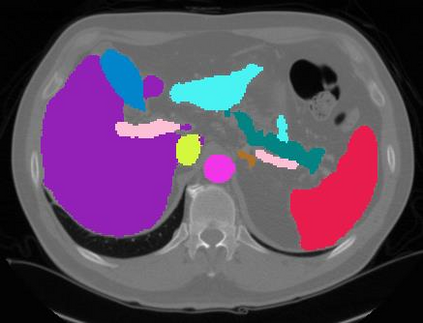

Vision transformers, with their ability to more efficiently model long-range context, have demonstrated impressive accuracy gains in several computer vision and medical image analysis tasks including segmentation. However, such methods need large labeled datasets for training, which is hard to obtain for medical image analysis. Self-supervised learning (SSL) has demonstrated success in medical image segmentation using convolutional networks. In this work, we developed a \underline{s}elf-distillation learning with \underline{m}asked \underline{i}mage modeling method to perform SSL for vision \underline{t}ransformers (SMIT) applied to 3D multi-organ segmentation from CT and MRI. Our contribution is a dense pixel-wise regression within masked patches called masked image prediction, which we combined with masked patch token distillation as pretext task to pre-train vision transformers. We show our approach is more accurate and requires fewer fine tuning datasets than other pretext tasks. Unlike prior medical image methods, which typically used image sets arising from disease sites and imaging modalities corresponding to the target tasks, we used 3,643 CT scans (602,708 images) arising from head and neck, lung, and kidney cancers as well as COVID-19 for pre-training and applied it to abdominal organs segmentation from MRI pancreatic cancer patients as well as publicly available 13 different abdominal organs segmentation from CT. Our method showed clear accuracy improvement (average DSC of 0.875 from MRI and 0.878 from CT) with reduced requirement for fine-tuning datasets over commonly used pretext tasks. Extensive comparisons against multiple current SSL methods were done. Code will be made available upon acceptance for publication.